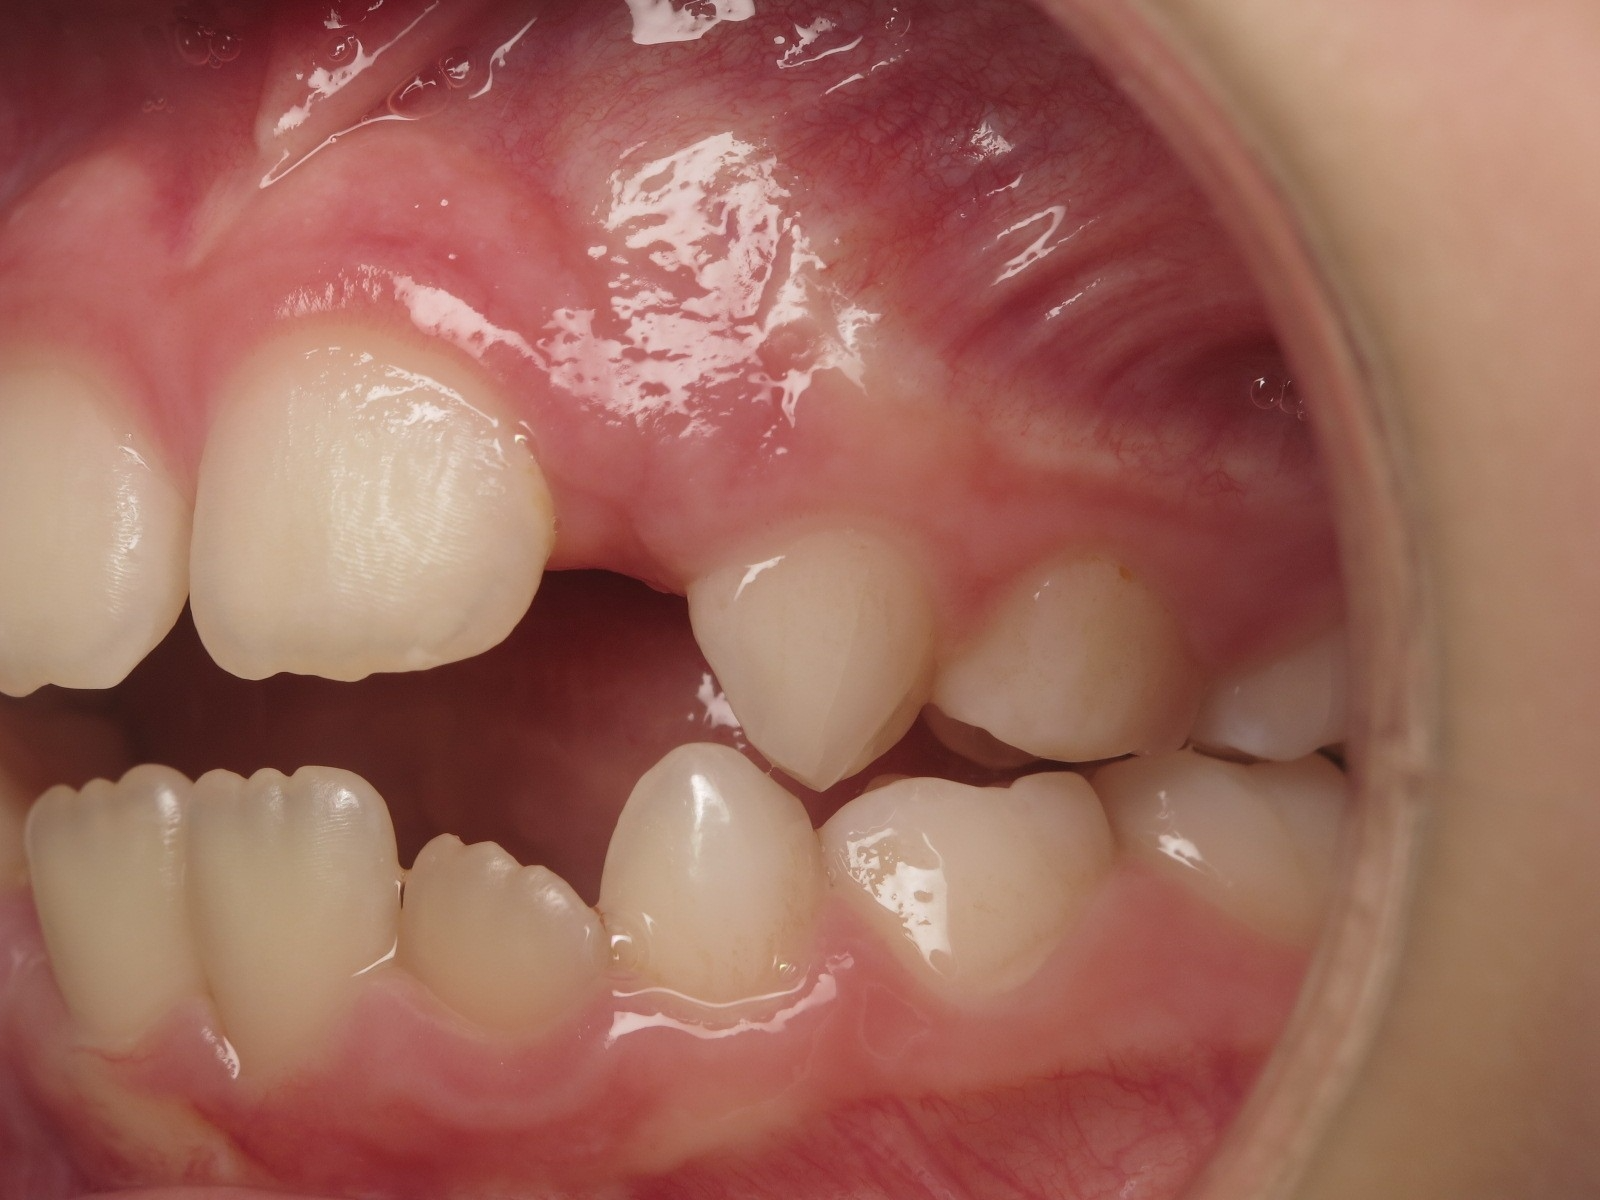

appareillage mobile pendant 14 mois

sectionnel multibagues pendant 8 mois